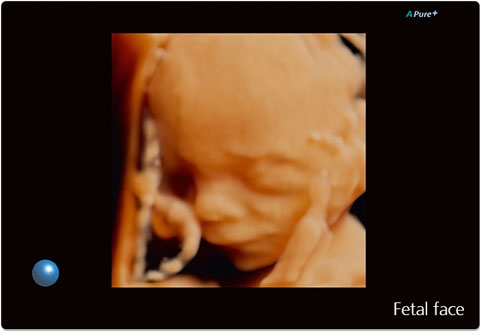

• ApliPure - технология повышения качества изображения

• Precision Imaging - технология получения изображений мелких деталей с четко очерченными границами и высокой однородностью

ApliPure:

Precision Imaging: